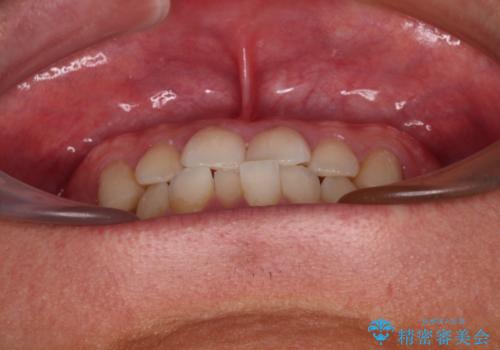

今回ご紹介するのは、「前歯のガタガタ(叢生)」と「奥歯のかみ合わせ(シザーズバイト)」にお悩みでご来院された患者様の症例です。

▼ 診断

・上顎左右の第二大臼歯が頬側へ転移し、シザーズバイト(scissors bite)の状態

・上顎左側第二小臼歯が90度捻転しており、噛み合わせに影響

**前歯のデコボコ(叢生)**が整い、歯列全体が美しく改善

シザーズバイトの奥歯も正常なかみ合わせに改善

捻転歯も回転が修正され、全体的に清掃性・咀嚼効率が向上